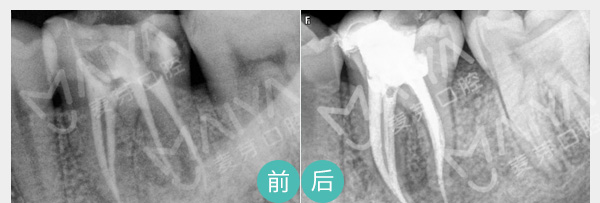

麦芽显微根管治疗

通过机械和化学方法去除根管内感染物,通过充填根管、封闭冠部,防止发生根尖周病变或促进发生的根尖周病变的愈合。

适应症:深度龋齿